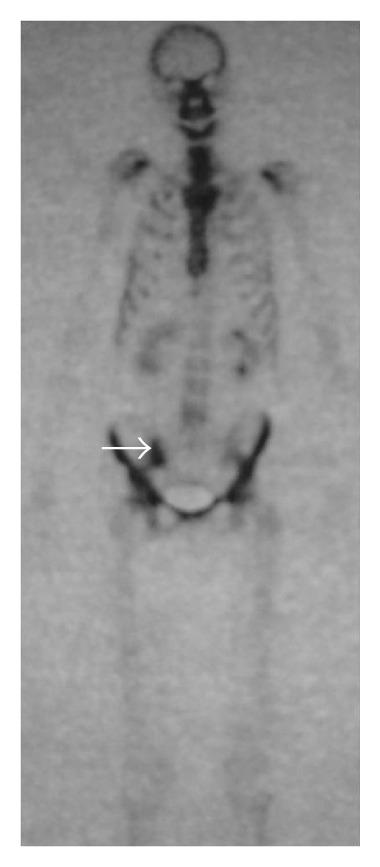

Pyogenic sacroiliitis and pyomyositis are uncommon infectious diseases and their diagnoses are often delayed. They are typically seen in children and young adults and are rare in middle-aged people especially in those affected by rheumatic diseases. We present the first case of a Staphylococcus aureus related pyogenic sacroiliitis associated with iliacus and gluteal pyomyositis occurring in a patient with systemic lupus erythematosus. Antibiotic treatment was administered for a total of 6 weeks with a total recovery. Pyogenic sacroiliitis and pyomyositis, although remaining rare events, should be remembered as severe complications in immunosuppressed patients with inflammatory diseases. Early clinical suspicion, imaging diagnosis, and adequate therapy are decisive for the satisfactory outcome.

化脓性骶髂关节炎和脓性肌炎是罕见的感染性疾病,其诊断常常延迟。它们通常见于儿童和年轻人,在中年人中罕见,尤其是在患有风湿性疾病的人群中。我们报告了首例与金黄色葡萄球菌相关的化脓性骶髂关节炎,该病例伴有髂肌和臀肌脓性肌炎,发生在一名系统性红斑狼疮患者身上。给予抗生素治疗共6周,患者完全康复。化脓性骶髂关节炎和脓性肌炎虽然仍然是罕见病症,但应被视为炎症性疾病免疫抑制患者的严重并发症。早期临床怀疑、影像学诊断和充分治疗对取得满意疗效至关重要。